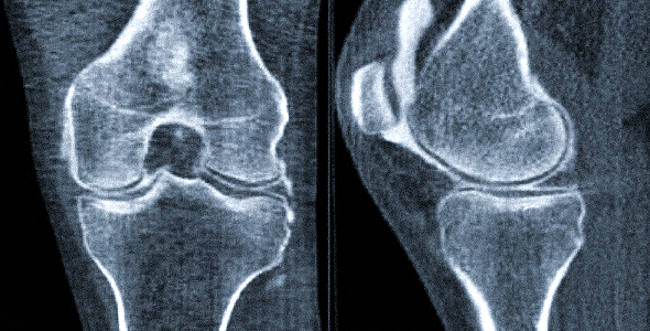

С помощью компьютерной томографии можно получить отчетливые снимки-срезы любых суставов. На снимках хорошо видны суставные поверхности, межсуставные щели, участки костей, формирующие сочленение. Менее отчетливо визуализируются мышечные ткани и связки.

Благодаря проведению томографии диагностируют патологии воспалительного, дегенеративно-дистрофического или опухолевого характера. Наиболее точно КТ суставов выявляет изменения в костных тканях, а также свежие травматические повреждения (гематомы, кровоизлияния).

Для выявления заболеваний суставов могут применяться оба обследования. Что лучше, КТ или МРТ сустава, зависит от цели диагностического поиска, наличия противопоказаний к тому или иному виду исследования. Компьютерная томография лучше визуализирует костные ткани, поскольку рентгеновские лучи хорошо ими поглощаются. Также на полученных изображениях отчетливо видны свежие травмы, повреждения, кровоизлияния. Компьютерную томографию, в отличие от МРТ, можно выполнять людям с установленными металлическими имплантами или электронными устройствами. Однако данный вид исследований противопоказан во время беременности и ограниченно применяется у детей.